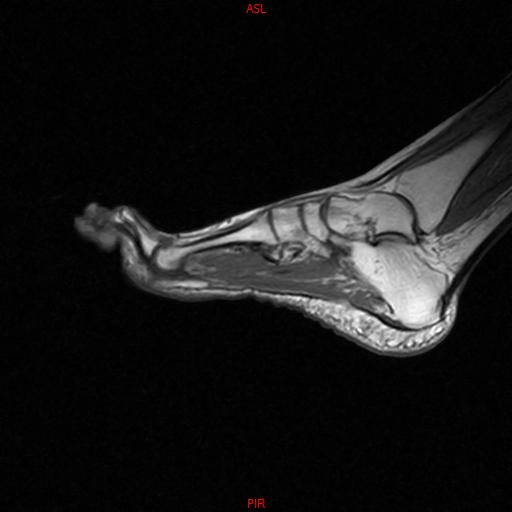

• Resonancia NORMAL PIE SAG T1